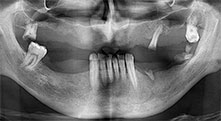

Could you describe briefly, for example, your procedure for mobilizing bone blocks for transplantation?

Bratu: We prefer to harvest bone from the external oblique ridge of the posterior mandible, not from the interforaminal region. After the soft-tissue incision, we use the new saws to define the amount of bone to harvest. With this approach, we also use them for the entire preparation in almost 80% of cases. We may also use other piezo instruments and then at the end a chisel to mobilize the block. We find that this is a very effective surgical technique.

Bratu: We routinely use the instruments for harvesting bone blocks and splitting alveolar ridges. We also use the Piezomed B6/B7 for osteotomy of impacted teeth and removing failed implants. All indications that require deep, clean cuts.